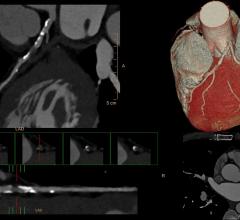

Feature | CT Angiography (CTA) | Dave Fornell

The Society of Cardiovascular Computed Tomography (SCCT) annual meeting offers an in-depth review of all aspects of…

Videos | CT Angiography (CTA)

DAIC/ITN editor Dave Fornell shows some of the most innovative new cardiac CT and angiography technologies from…